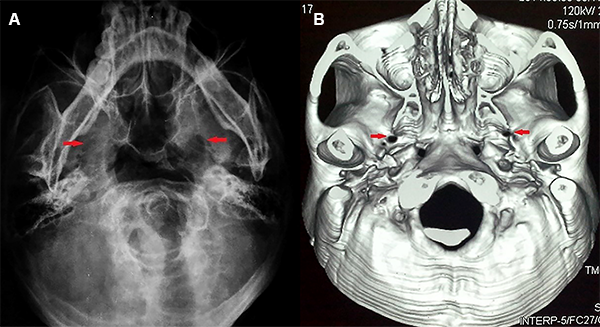

La resonancia magnética de encéfalo fue realizada con una combinación de tres secuencias de alta resolución (3D ponderada en T2, 3D TOF-MRA y 3D T1-Gad) para la detección de un posible contacto neurovascular con cortes finos en los nervios trigéminos. Los agujeros ovales fueron evaluados con radiografías o tomografía computarizada de base cráneo (Figura 2A y 2B).

Figura 2: (A) Radiografía en incidencia de submento-vértical. (B) Tomografía computarizada con reconstrucción 3D de base del cráneo. Las flechas muestran los agujeros ovales.